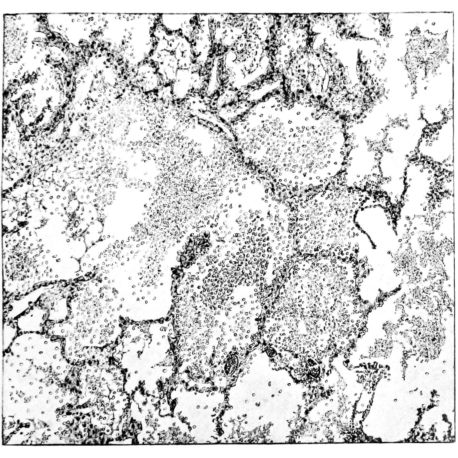

FIG. II. AUTOPSY NO. 98. DRAWING OF A SECTION THROUGH A TRACHEA SHOWING NECROTIZING HEMORRHAGIC INFLAMMATORY PROCESS OF THE MUCOSA.